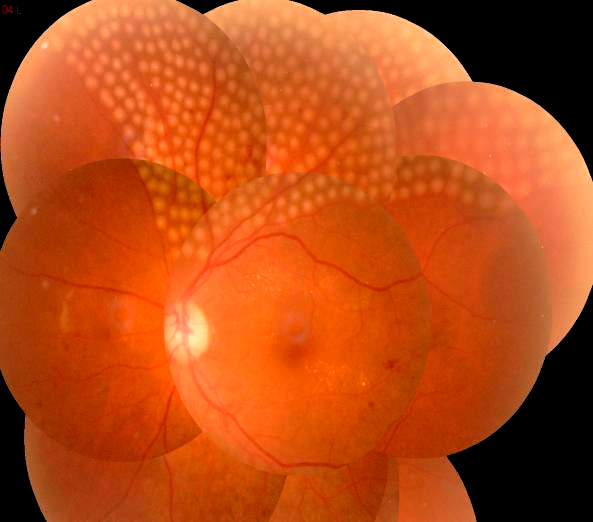

近年来,随着高血压、糖尿病、高血脂等患者的增多,这些疾病导致的视网膜静脉阻塞、糖尿病视网膜病变、黄斑水肿等眼底并发症的发病率有逐年增高的趋势。我院眼科在临床治疗工作中,发现患有眼底疾病的患者明显增多,而这些眼底疾病需要早筛查、早发现、早治疗,如果等到晚期出现视网膜脱离等严重并发症,等待患者的将是永久的失明。

视网膜激光光凝术是治疗眼底疾病的主要方法。利用激光的热效应,作用于眼底的病变部位,使之被光凝破坏形成瘢痕,从而达到封闭或破坏缺氧区的治疗技术,可以有效地控制视网膜细胞的代谢,减少视网膜水肿渗出、减轻黄斑水肿、改善视网膜供氧、抑制新生血管形成,阻止视网膜病变的进展,防止视网膜遭到进一步的损害。

常用于糖尿病视网膜病变、视网膜静脉阻塞、视网膜血管炎、视网膜血管瘤、中心性浆液性脉络膜视网膜病变、外层渗出性视网膜病变、家族性渗出性视网膜病变、早产儿视网膜病变、视网膜裂孔、视网膜变性等。